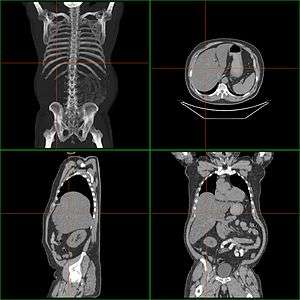

| Computerized tomography of hepatomegaly | |

A complete blood test can help distinguish intrinsic liver disease from extrahepatic bile-duct obstruction.[13] An ultrasound of the liver can reliably detect a dilated biliary-duct system,[14] it can also detect the characteristics of a cirrhotic liver,.[15]Computerized tomography (CT) can help to obtain accurate anatomical information, in individuals with hepatomegaly.[16]